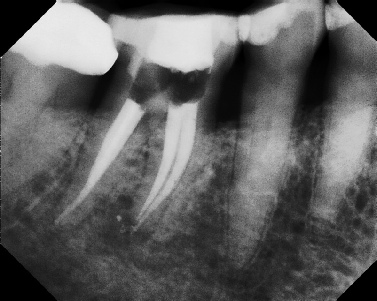

COMPLICATED ANATOMY LARGE LESIONS CALCIFIED CANALS PERFORATION / RESORPTION SEPARATED INSTRUMENTS SURGICAL CASES RETREATMENT / pOST REMOVAL OPEN APICES ACCESS THRU CROWNS Root Canal Case Portfolio